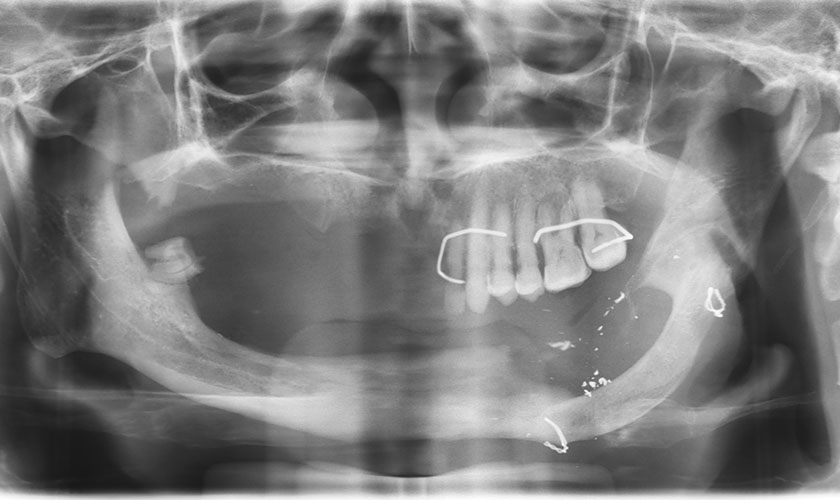

Hình chụp trong miệng và phim X-quang trình trạng của bệnh nhân trước khi điều trị

Trường hợp của bệnh nhân, qua khảo sát phim X-quang cắt lớp và sử dụng phần mềm để tái lập lại cấu trúc 3 chiều của xương hàm cho thấy: có sự tiêu xương hàm dưới trầm trọng, thần kinh răng dưới có lộ trình bất thường kéo dài từ bên phải băng qua đường giữa và sang bên trái.

Thậm chí thần kinh lộ trên sống hàm ở một vài vị trí nên không thể cấy implant theo kỹ thuật thông thường. Chiều cao xương từ đỉnh sống hàm đến thần kinh răng dưới chỉ còn 1 - 2 mm không đủ để cấy implant có chiều dài thích hợp (10 mm) và an toàn (nguyên tắc là implant phải cách thần kinh 2 mm).

Hình chụp Xquang Panorex của bệnh nhân